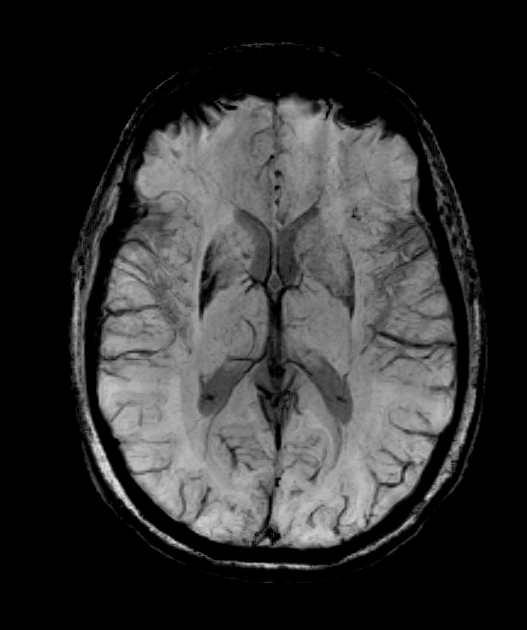

- 80-year-old patient presented with asymmetric parkinsonism (left > right) with freezing and early falls with poor response to levodopa.

- MRI showed putaminal atrophy, susceptibility artefact and T2-hyperintensity along the lateral aspect of the putamina.